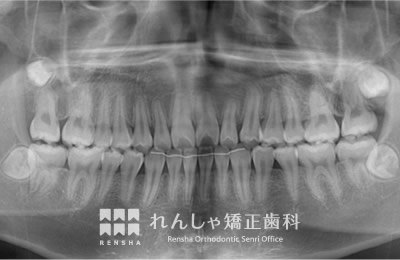

中高生

永久歯列はほぼ完成してしますが、歯列を側方だけでなく後方へも拡大し、埋まっていた右上奥歯を引っ張り出しています。

| 主訴 | 埋まったままでてこない歯がある |

|---|---|

| 診断名 | Angle Class II 小臼歯の埋伏と叢生を伴う上顎前突 |

| 初診時年齢 | 13歳5か月 |

| 装置名 | マルチブラケット装置 |

| 抜歯非抜歯 | 非抜歯 |

| 治療期間 | 2年3か月 |

| 費用の目安 | 約82万円+消費税(検査料金、都度の処置費用等も合わせた総額) |

| リスク副作用 | 歯の移動に伴う軽微な歯根吸収、歯槽骨吸収、歯肉退縮(本症例では軽度の歯根吸収を認めた)、矯正器具装着中のカリエスリスク増大(本症例ではカリエス発生無し) |